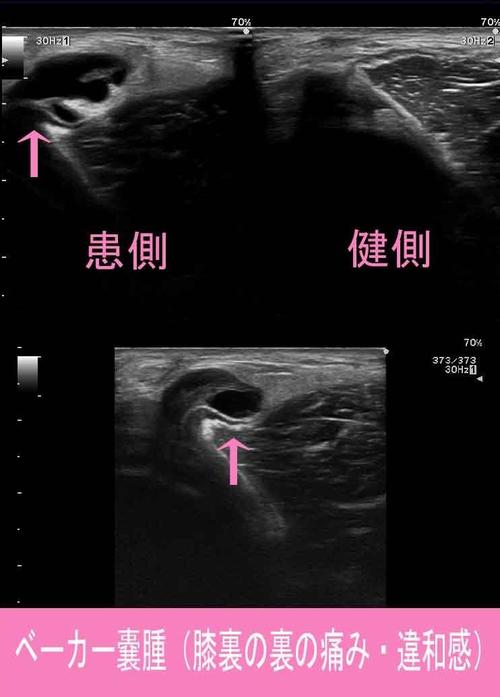

日常生活や運動後などに「膝の裏が腫れている」

「膝を曲げると痛み・違和感がある」という症状は

"ベーカー嚢腫"というものかもしれません。

ベーカー嚢腫とは、膝の裏にある滑液包と関節包が

交通しており、膝関節部の滑液が滑液包へ流れ込み、

貯留して膨らんだものです。